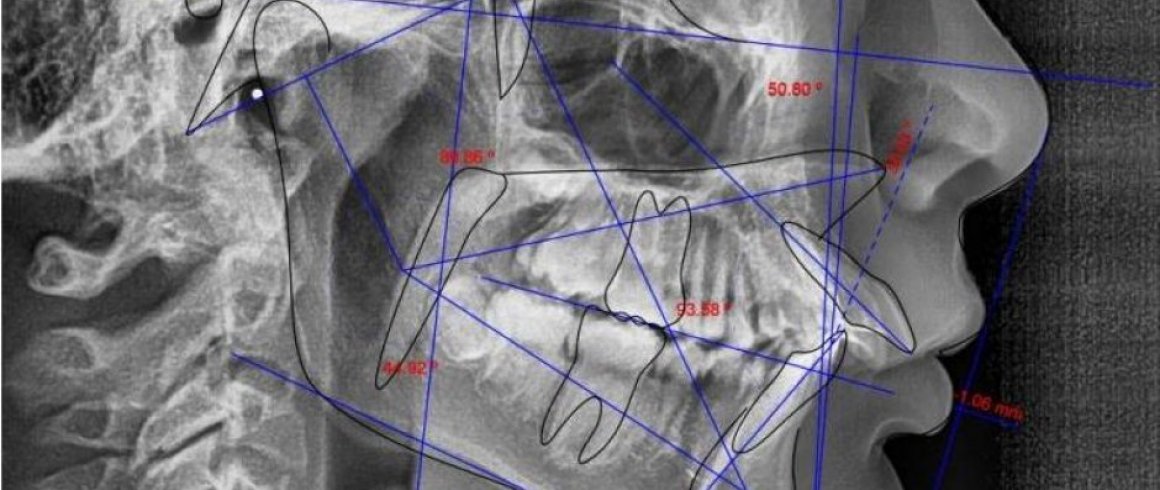

- Análisis Cefalométrico Lateral